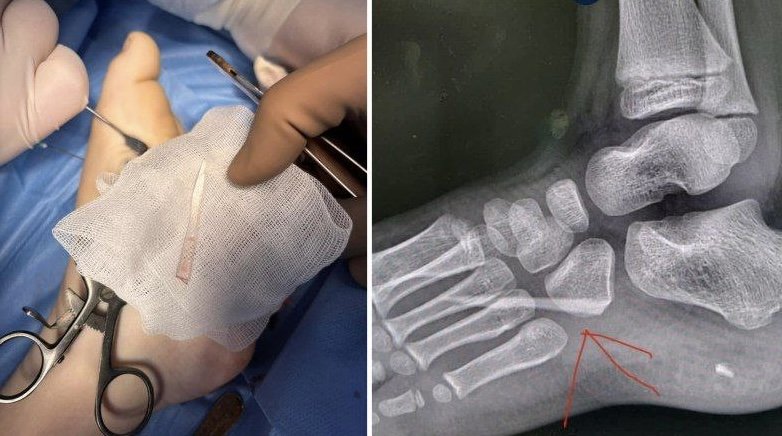

На Закарпатті лікарі успішно прооперували 7-річну дитину з аутизмом, у стопі якої виявили великий уламок скла.

Як розповіли батьки, дитина почала накульгувати, але не скаржилася на біль. Після звернення до медиків у травматолого-ортопедичному відділенні лікарні провели клінічний огляд та рентген, під час якого і виявили стороннє тіло.

Хірургічне втручання пройшло успішно — уламок скла видалили без ускладнень, стан дитини задовільний.